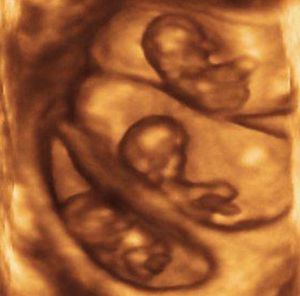

Why twins if you can have triplets right away. ❤️

We present you an amazing 3D ultrasound image of triplets at 11 weeks of gestation.